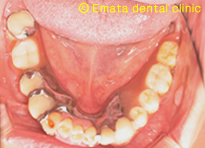

![]() |

奥歯の骨が少ないです。 |